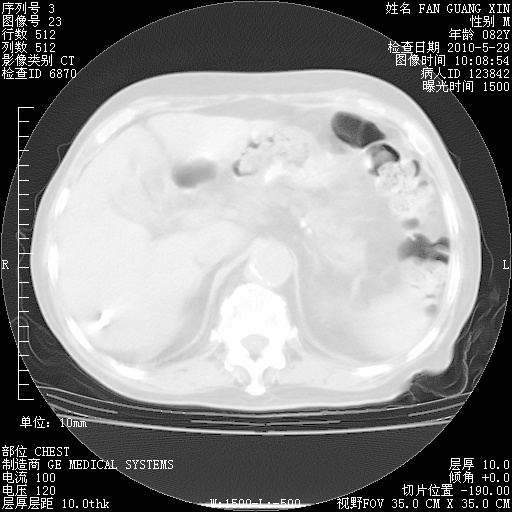

再治疗10天后的肺部CT 纵膈窗

阅读此次胸部CT,肺间质渗出性改变较入院时有吸收。目前从体温、白细胞、中性分叶明显增高,肯定存在细菌感染(发生医院感染哦,若无消化道及泌尿系统等感染的依据,肺部感染可能大)。若你院头孢哌酮舒巴坦钠耐药率较高,同意你的方案,若48小时体温仍高,可考虑使用碳青霉稀类抗菌药物,同时可予超声雾化、注意滴数时加大液体量。白蛋白33.30g/L较低哦,需加强营养等支持治疗。